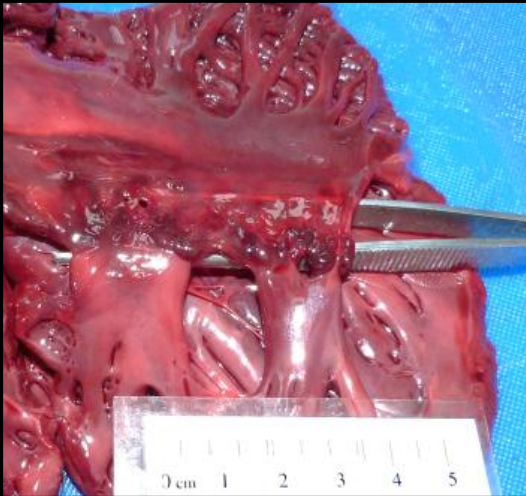

Which kidney is abnormal?

TOP

What term is best used to describe the top kidney?

enlarged

What has been done to these kidneys?

hemisectioned

What does this image show?

cut surface of the abnormal kidney

cut surface of the normal kidney

What type of pathological change is most likely to have affected the renal parenchyma?

atrophy

What has caused the parenchymal atrophy?

pressure build up repressing blood supply to tissue